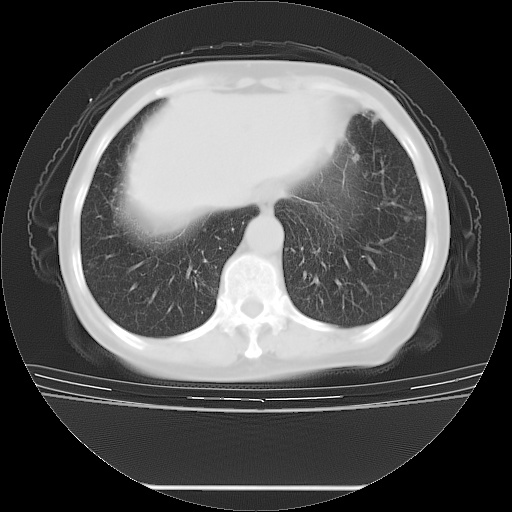

患者女性,72岁,慢性咳嗽3月余,曾抗炎治疗无效果,最近抗结核治疗约半月余,症状缓解。

ct示两肺粟粒状病灶,以两肺上叶尖后段及下叶背段分布为主;首先考虑结核。请战友们分析。

考虑 1 弥漫性泛细支气管炎, 2 结核不除外/.  有小叶中心结节 和 树芽征!!

两肺内病灶呈小结节状和树芽状,纵膈的肿大的淋巴结密度不均匀,并见有钙化,考虑为两肺结核可能更大些。

两肺内病灶呈小结节状和树芽状,纵膈的肿大的淋巴结密度不均匀,并见有钙化,多形态病灶,考虑为两肺结核,肝内考虑小囊肿。

病灶以结节为主,大部分边界清楚,分布不均,病灶形态较单一,偶见空泡征,纵膈淋巴结肿大钙化,无结核中毒症状考虑 感染性病变【真菌类可能性大】,细支气管肺泡癌。其他待排

两肺内病灶呈小结节状和树芽状,纵膈的肿大的淋巴结密度不均匀,并见有钙化,结合(曾抗炎治疗无效果,最近抗结核治疗约半月余,症状缓解。)

考虑为两肺结核可能更大些。